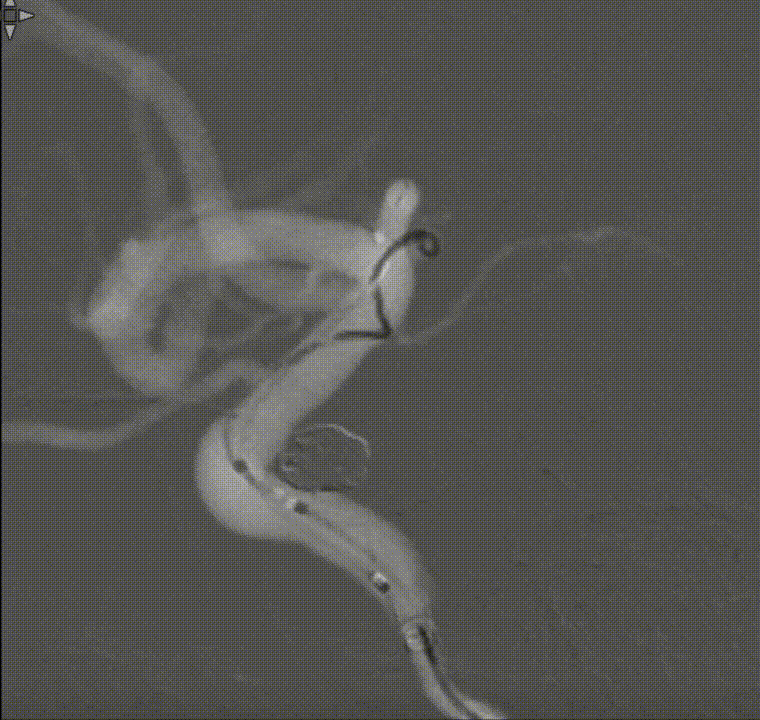

通过璞慧0.017微导管填入Target 1.5/2弹簧圈部分成篮,后释放Atlas 3.0/15支架覆盖瘤颈处,继续填入弹簧圈时微导管脱出,尝试用弹簧圈将微导管引导超选瘤腔失败。

撤出弹簧圈,Asahi 0.014微导丝引导璞慧 0.017微导管穿支架网孔进入动脉瘤内。

继续填入Target 1.5/2弹簧圈成篮,后完全释放支架,其近端位于颈内动脉分叉处,远端位于A1远端。

填入第一枚弹簧圈

通过调整栓塞微导管的张力继续填入Target 1/3弹簧圈。

术后正侧位造影:Raymond Ⅲ级

术后支架重建:支架打开良好,近端Marker位于颈内动脉分叉处